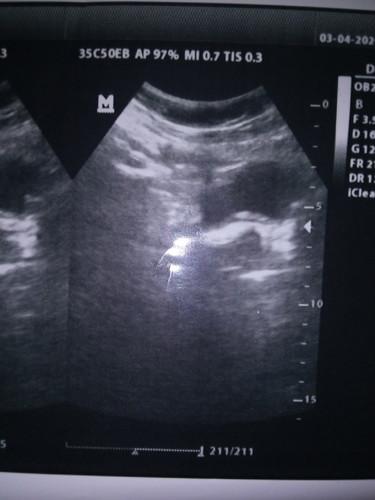

mau tanya bun .?? apa ini hamil kosong tapi kok ada putih" nya . aku udah telat 13 minggu .

Gimana ya bun